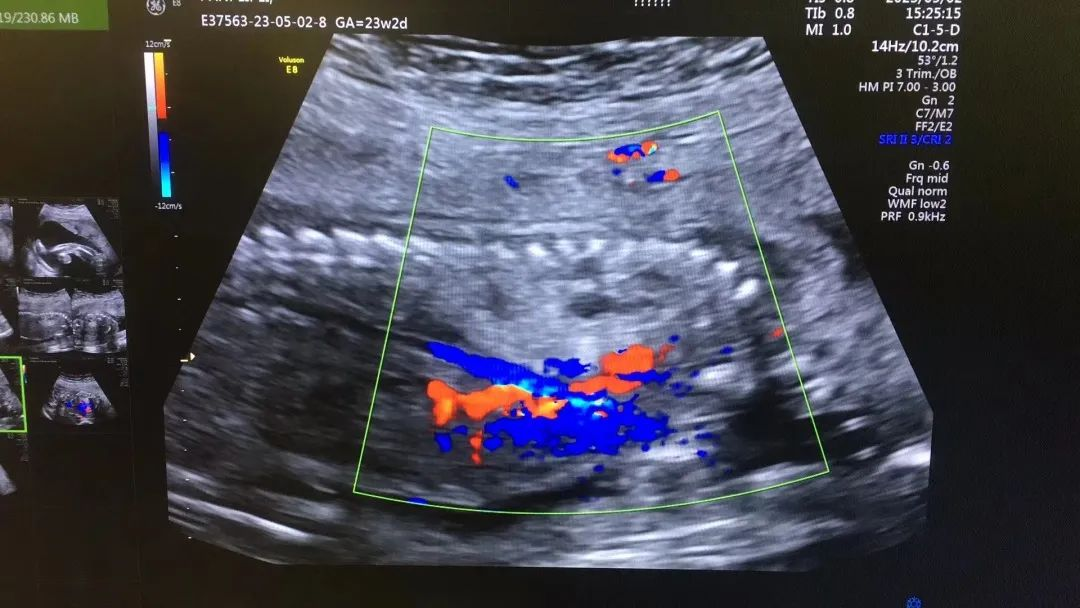

武漢的劉女士(化名),前幾個(gè)月剛懷上寶寶,全家都特別高興。懷孕23周+時(shí),劉女士在家人的陪伴下來到武漢仁愛醫(yī)院超聲科做了四維彩超檢查,當(dāng)醫(yī)生拿出檢查報(bào)告的時(shí)候,劉女士卻當(dāng)場傻眼了,原來,在四維彩超的報(bào)告里,診斷出了胎兒右肺囊性腺瘤樣病變,她的心頓時(shí)揪了起來!

劉女士看到檢查結(jié)果后,擔(dān)心該病變會(huì)影響腹中寶寶的健康,考慮是否應(yīng)該終止妊娠。隨即,武漢仁愛醫(yī)院超聲科王娟主任為劉女士耐心地解釋:“先天性肺囊腺瘤是一種肺組織錯(cuò)構(gòu)畸形,先天性肺囊腺瘤畸形病例約70%的腫塊大小較穩(wěn)定;約20%腫塊產(chǎn)前明顯縮小或消失;僅10%腫塊是進(jìn)行性增大。單純的先天性肺囊腺瘤(CCAM)無水腫的胎兒可以密切隨訪,在28周前接受連續(xù)超聲復(fù)查,CVR<1.6,一般超聲動(dòng)態(tài)監(jiān)測2~4周監(jiān)測一次,而對于CVR≥1.6的需要在28周前每周1-2次的超聲監(jiān)測,防止出現(xiàn)胎兒水腫,直到分娩。”